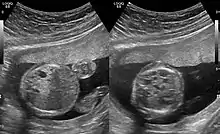

CPAMs are often identified during routine prenatal ultrasonography. Identifying characteristics on the sonogram include: an echogenic (bright) mass appearing in the chest of the fetus, displacement of the heart from its normal position, a flat or everted (pushed downward) diaphragm, or the absence of visible lung tissue.

CPAMs are classified into three different types based largely on their gross appearance. Type I has a large (>2 cm) multiloculated cysts. Type II has smaller uniform cysts. Type III is not grossly cystic, referred to as the "adenomatoid" type. Microscopically, the lesions are not true cysts, but communicate with the surrounding parenchyma. Some lesions have an abnormal connection to a blood vessel from an aorta and are referred to as "hybrid lesions."

Imaging

The earliest point at which a CPAM can be detected is by prenatal ultrasound. The classic description is of an echogenic lung mass that gradually disappears over subsequent ultrasounds. The disappearance is due to the malformation becoming filled with fluid over the course of the gestation, allowing the ultrasound waves to penetrate it more easily and rendering it invisible on sonographic imaging. When a CPAM is rapidly growing, either solid or with a dominant cyst, they have a higher incidence of developing venous outflow obstruction, cardiac failure and ultimately hydrops fetalis. If hydrops is not present, the fetus has a 95% chance of survival. When hydrops is present, risk of fetal demise is much greater without in utero surgery to correct the pathophysiology. The greatest period of growth is during the end of the second trimester, between 20–26 weeks.

A measure of mass volume divided by head circumference, termed cystic adenomatoid malformation volume ratio (CVR) has been developed to predict the risk of hydrops. The lung mass volume is determined using the formula (length × width × anteroposterior diameter ÷ 2), divided by head circumference. With a CVR greater than 1.6 being considered high risk. Fetuses with a CVR less than 1.6 and without a dominant cyst have less than a 3% risk of hydrops. After delivery, if the patient is symptomatic, resection is mandated. If the infant is asymptomatic, the need for resection is a subject of debate, though it is usually recommended. Development of recurrent infections, rhabdomyosarcoma, adenocarcinomas in situ within the lung malformation have been reported.[4]